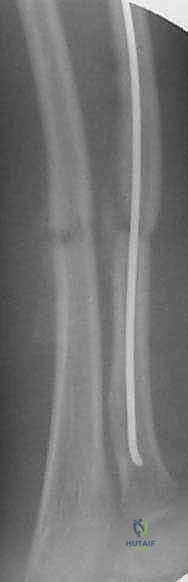

The nail is passed across the fracture site under live fluoroscopy.

The tip of the radial nail should be driven into the proximal radial metaphysis, ideally stopping just short of the proximal physis to avoid growth arrest.

Throughout this process, the surgeon must continuously verify fracture alignment, nail trajectory, and the restoration of the interosseous space on both AP and lateral fluoroscopic views.

The C-arm is used to confirm the final reduction, ensuring that length, alignment, and rotation are completely restored.

Final, static orthogonal radiographs are obtained to document the surgical outcome.